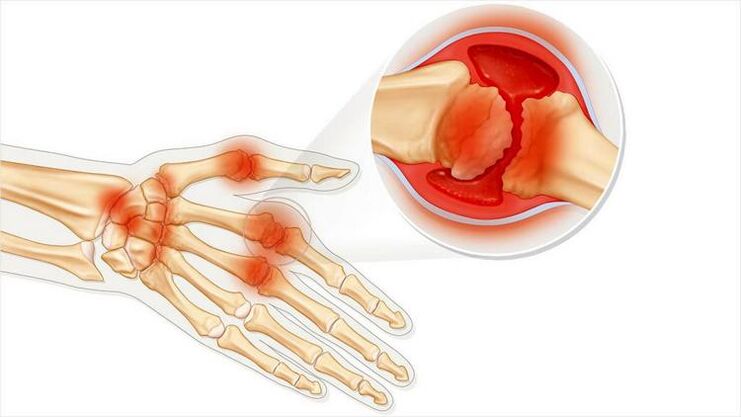

Artritis zgloba je stanje upale zglobova. Uglavnom izraženo kao oteklina i crvenilo. Uništena je unutarnja sluznica zgloba, što rezultira bolom koju je često teško izdržati.

oštećenje zglobova ruke zbog artritisa

Simptomi artritisa

Artritis karakteriziraju sljedeće značajke:

1. Može se pojaviti groznica ako koža u blizini zgloba postane crvena.

2. Promjena izgleda zgloba.

3. Tumor.

4. Bolne senzacije pri kretanju.

5. Neugodni senzacija prilikom pritiska na zglob.

6. Artritis može biti zarazna bolest. Tada se pojavljuju svi simptomi koji odgovaraju infekcijama: slomljeno stanje, groznica, zimica.

Artritis može utjecati na jedan zglob ili nekoliko. Javlja se kod akutne boli ili postepeno i uzrokuje kroničnu bolest. Tada dolazi do dosadne bolne boli.